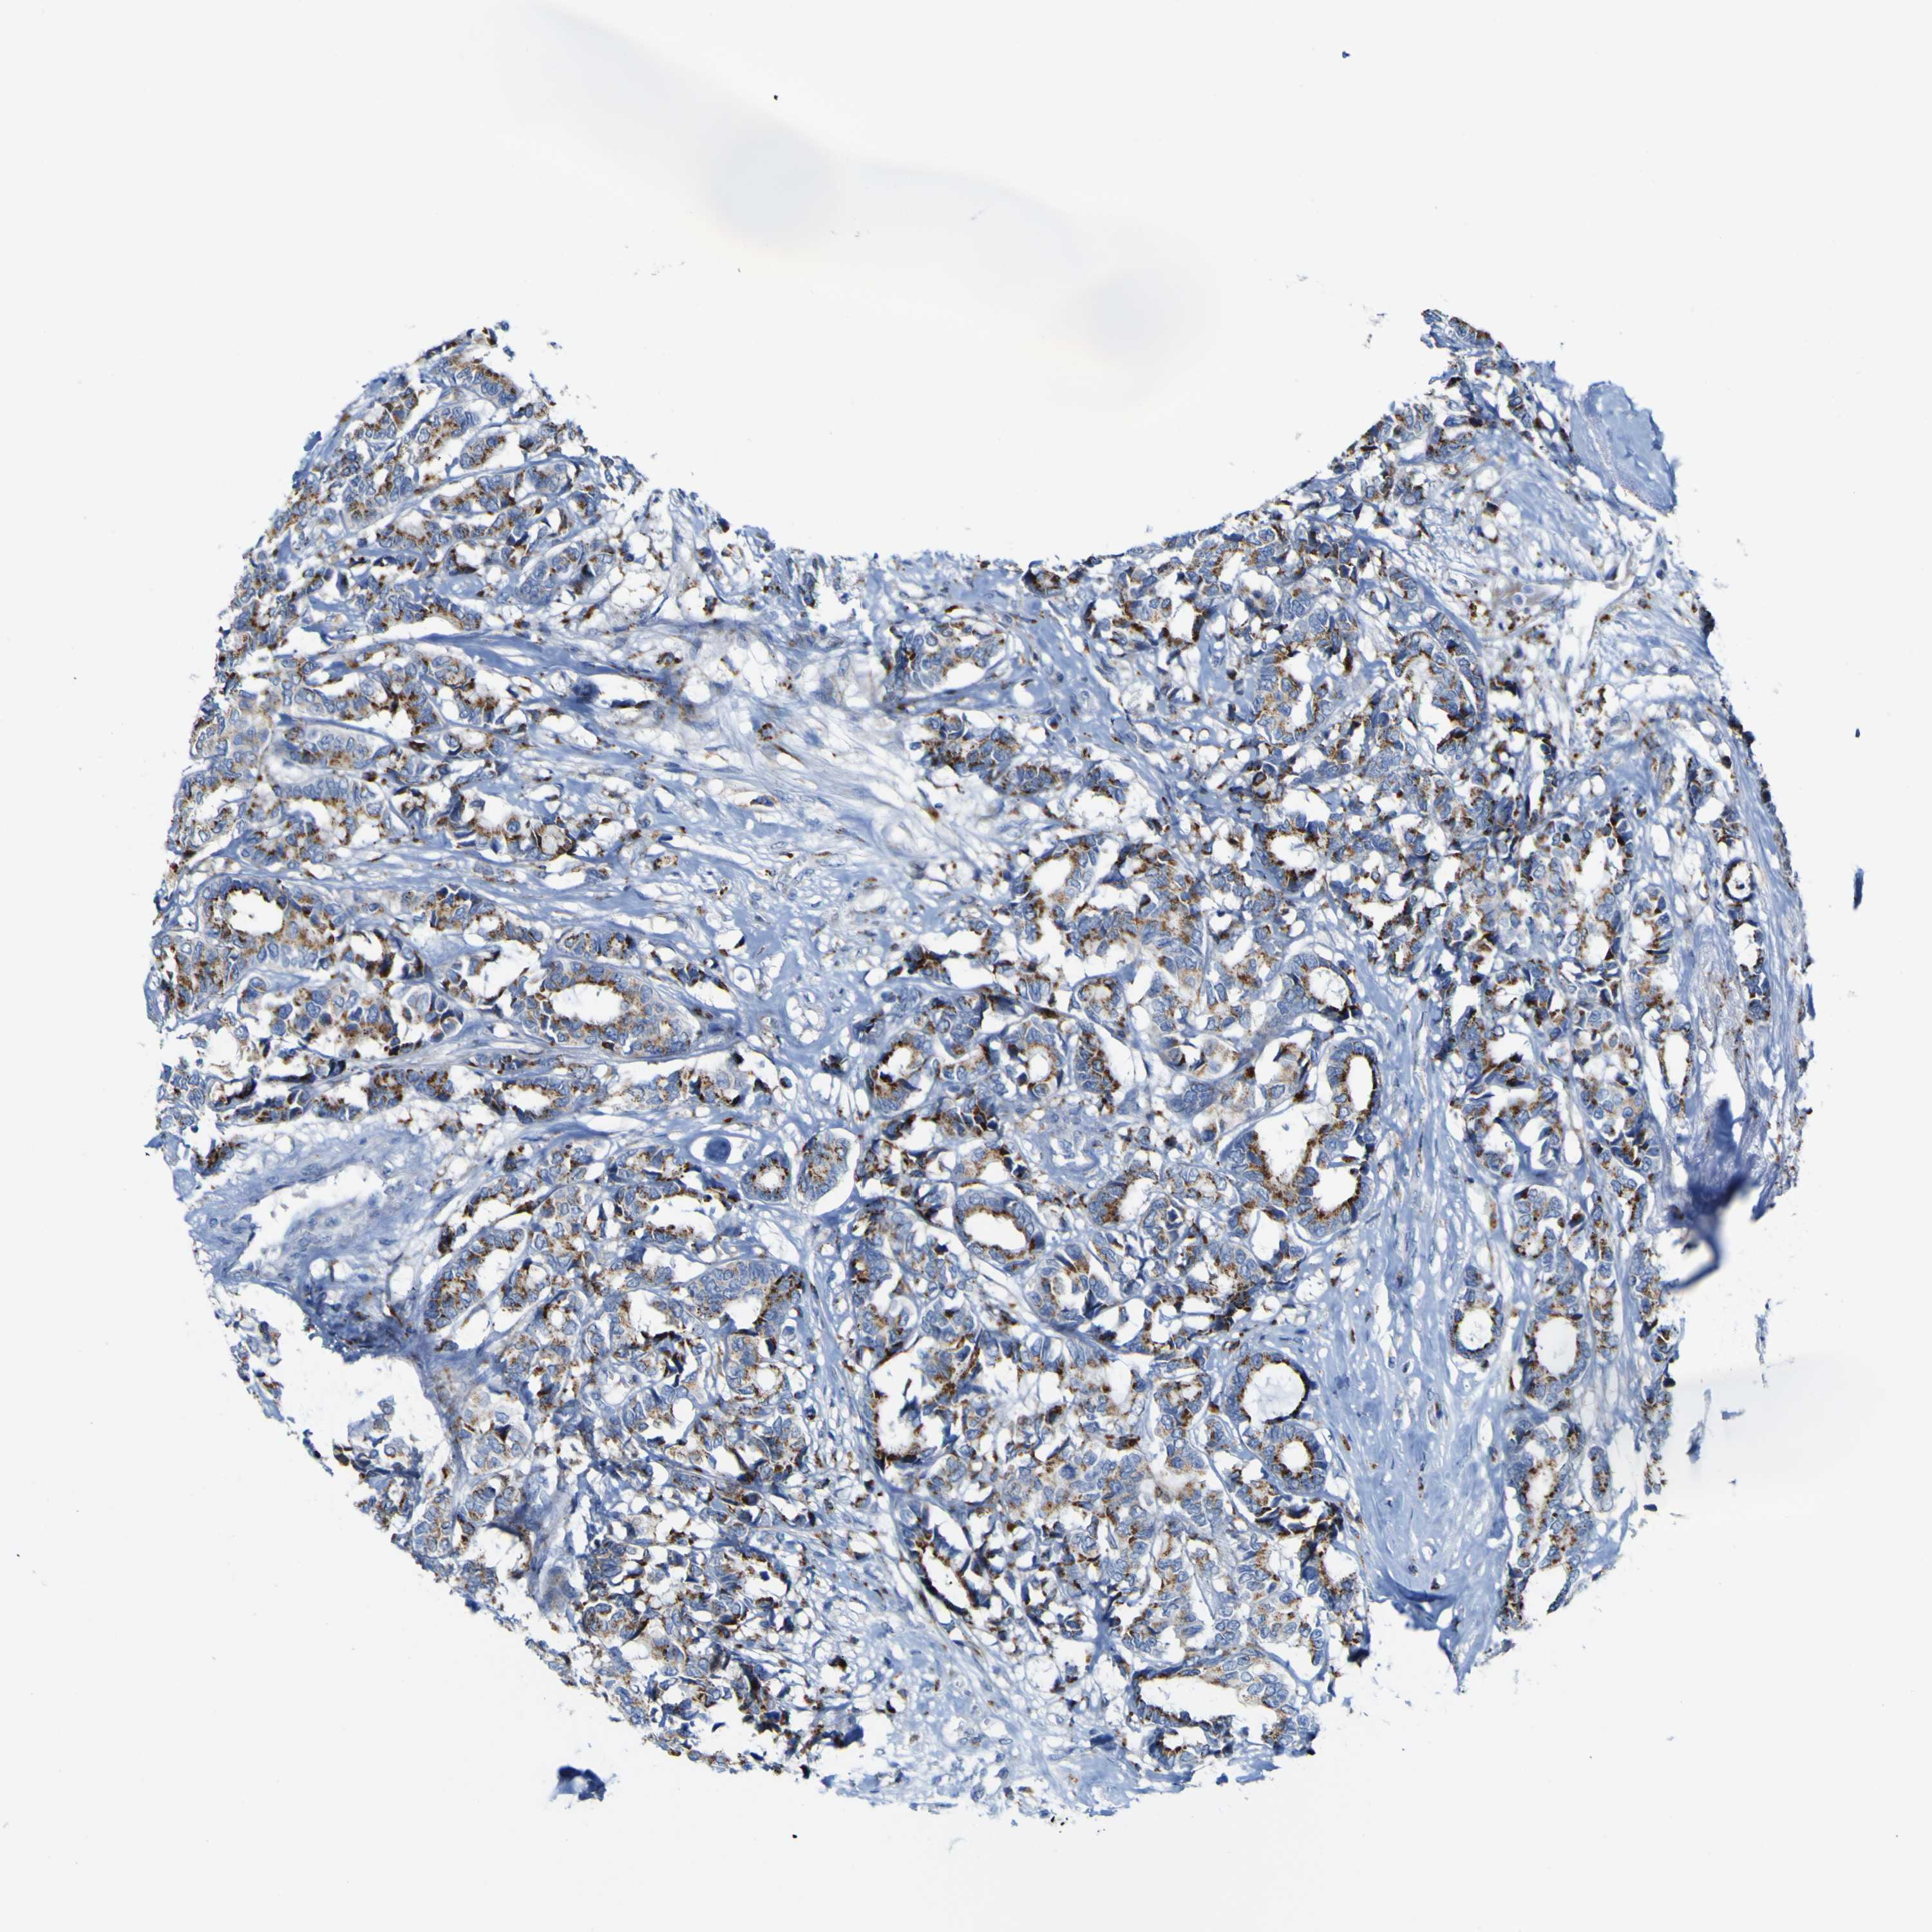

CANCER BREAST CANCER Show tissue menu

BRCA TCGA BRCA VALIDATION PROTEIN EXPRESSION